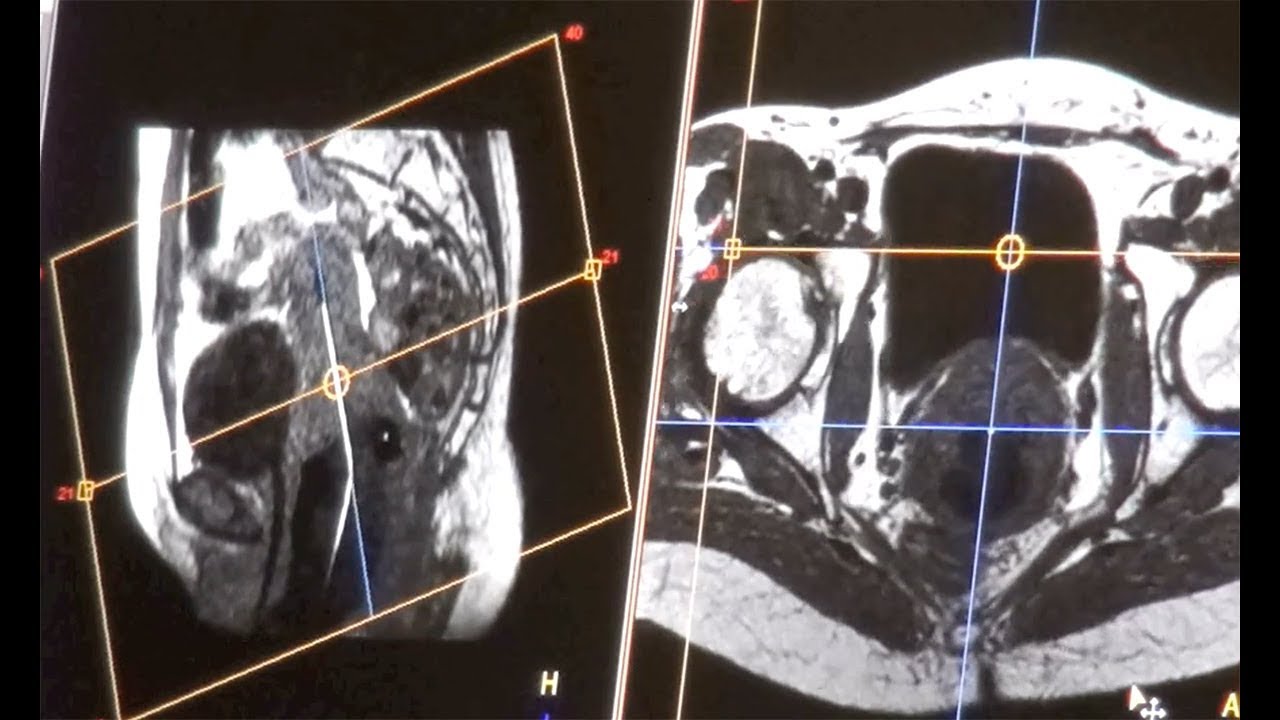

Rapid precision treatment for gynecological cancers YouTube

From www.youtube.com

Rapid precision treatment for gynecological cancers YouTube Radiosurgery Gynecological Cancer Reported survival outcomes of sbrt for a cohort of 30 patients with recurrent gynecological cancer. Findings from this systematic review suggest that in carefully selected patients with gynecologic cancer and limited macroscopic disease. A growing body of data supports the use of sbrt for oligometastatic/oligorecurrent gynecologic malignancies for. Radiosurgery Gynecological Cancer.